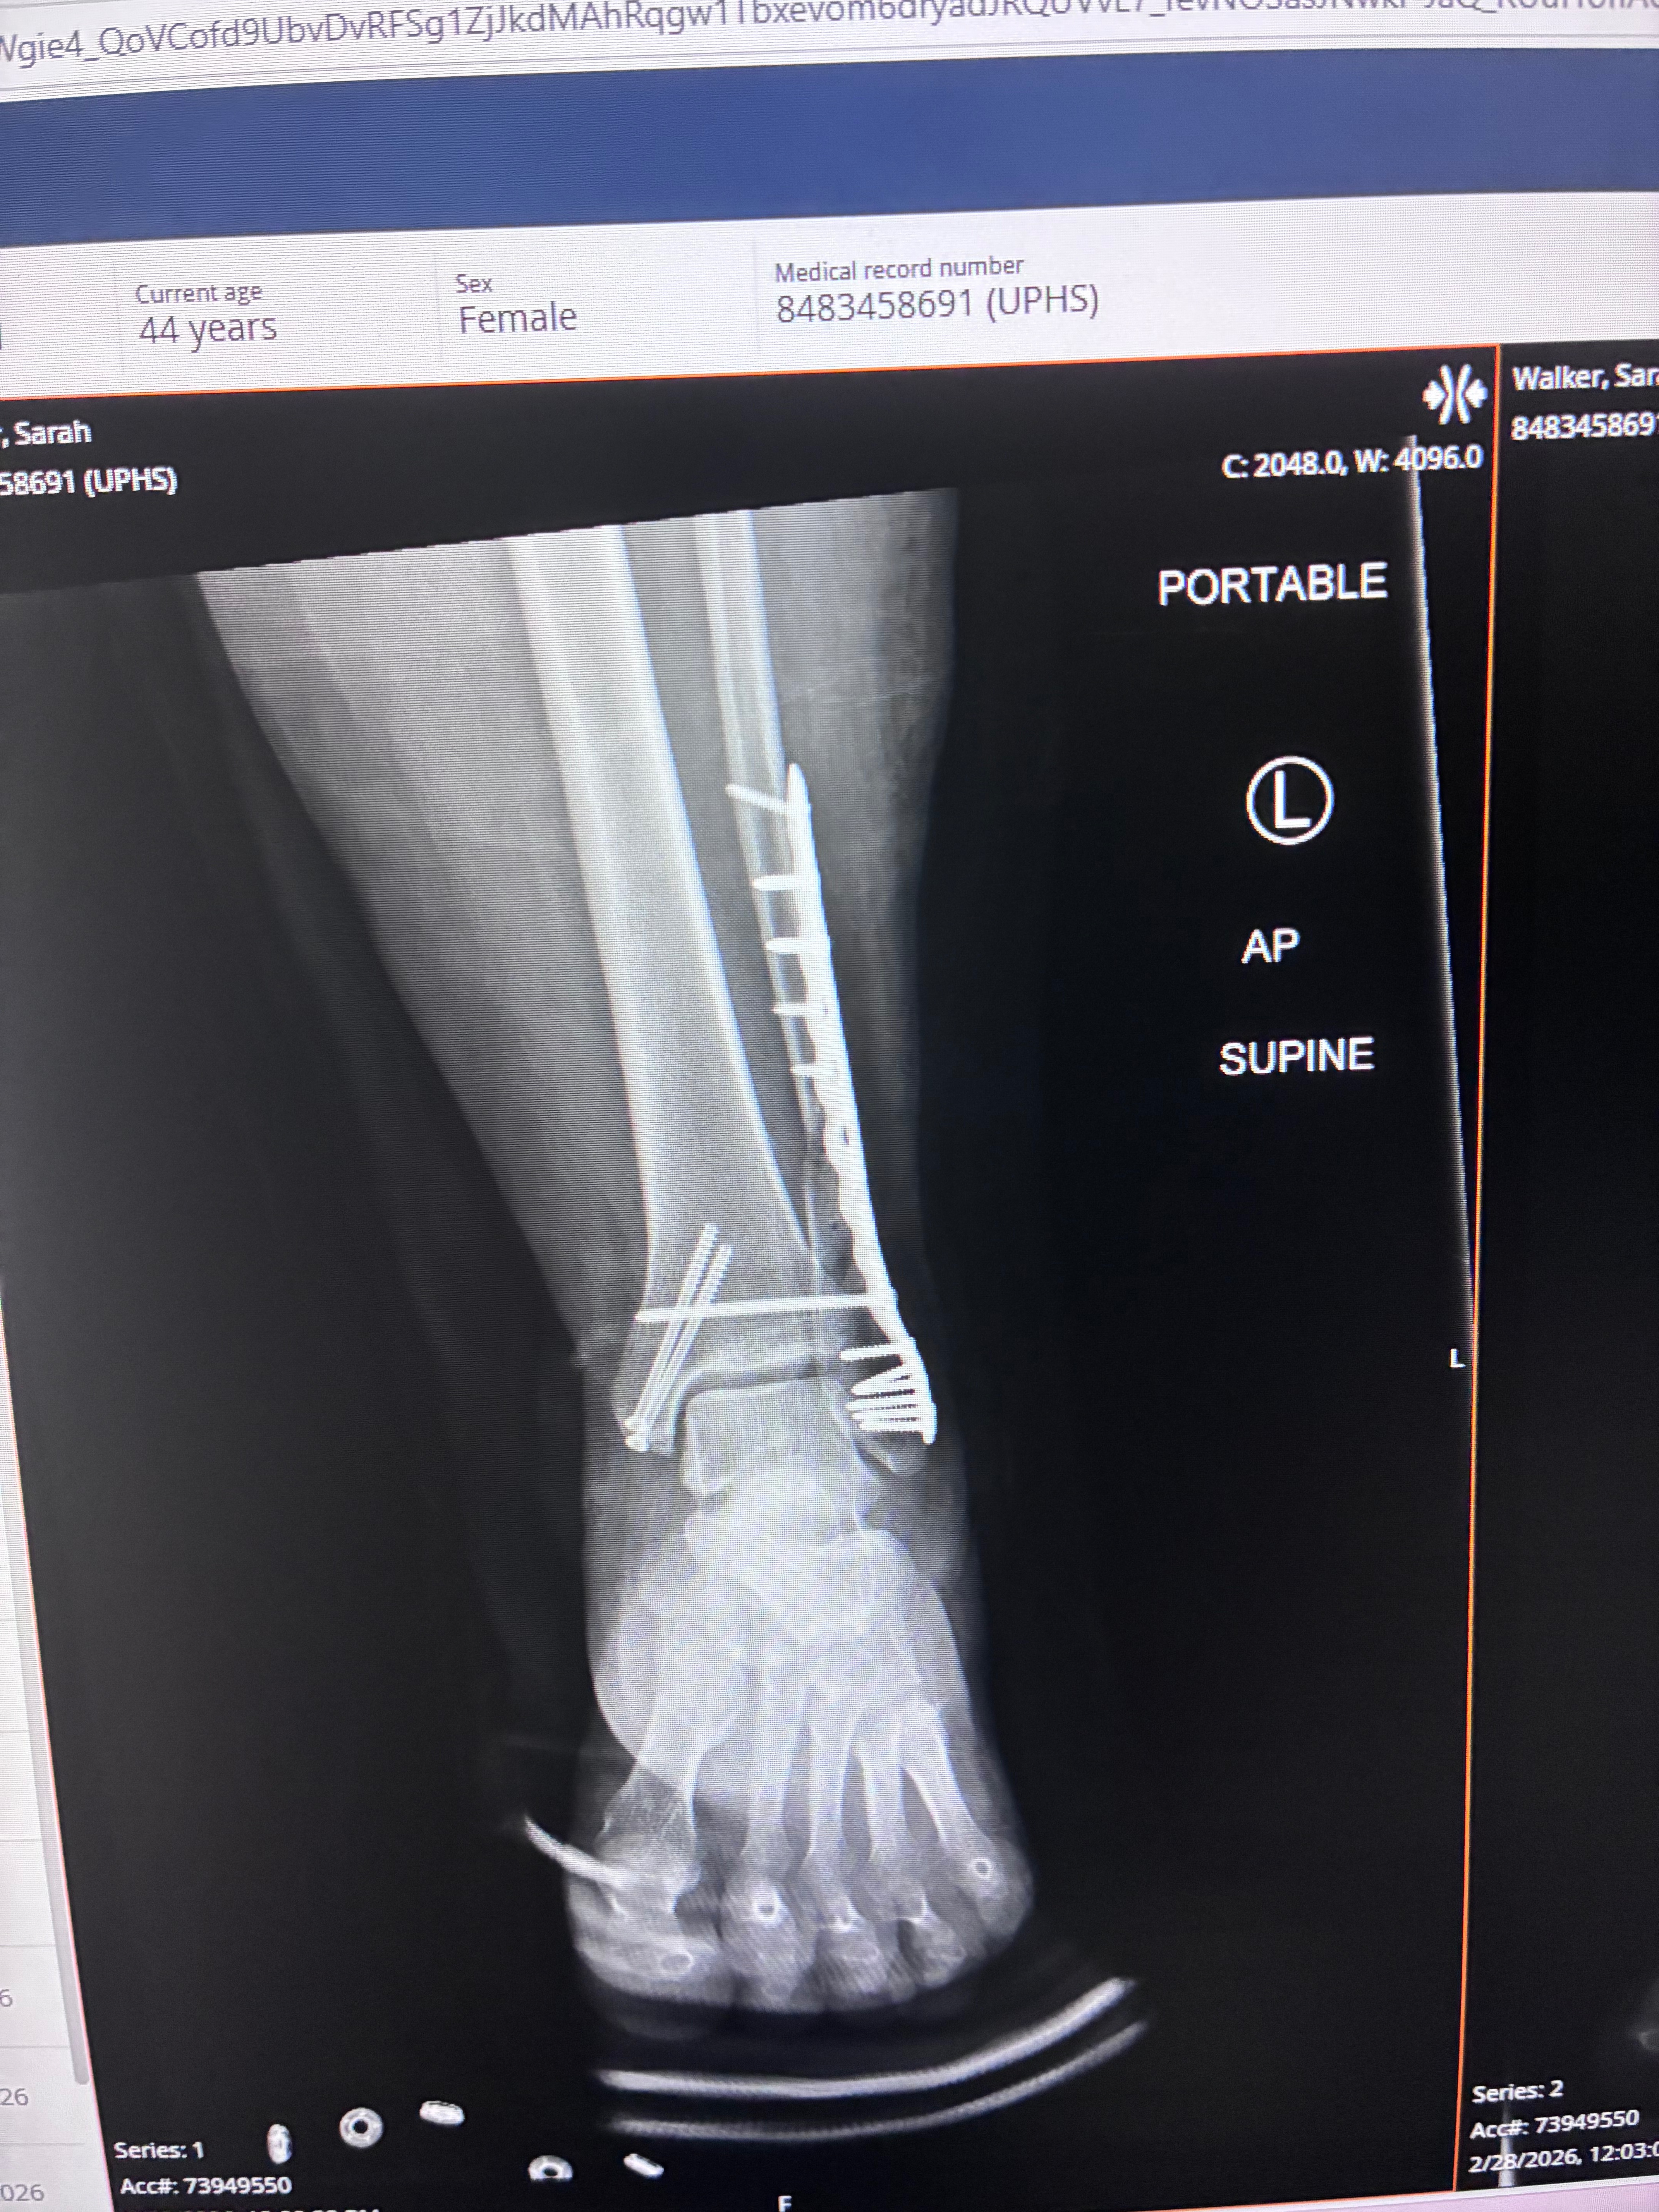

Hello, my name's Sarah, and on 2/24 I sustained a terrible injury. I slipped on ice and fell, which led to a compound fracture in my ankle and lower leg. My 10-year-old daughter placed the call to 911, while my 17-year-old daughter applied a tourniquet to my lower leg to stop the bleeding. I was rushed to the hospital where I underwent an emergency surgery to stop the bleeding and realign my bones. I've now received 2 surgeries, and I am currently recovering at home. I am unable to apply any weight to my leg, which means bed rest.